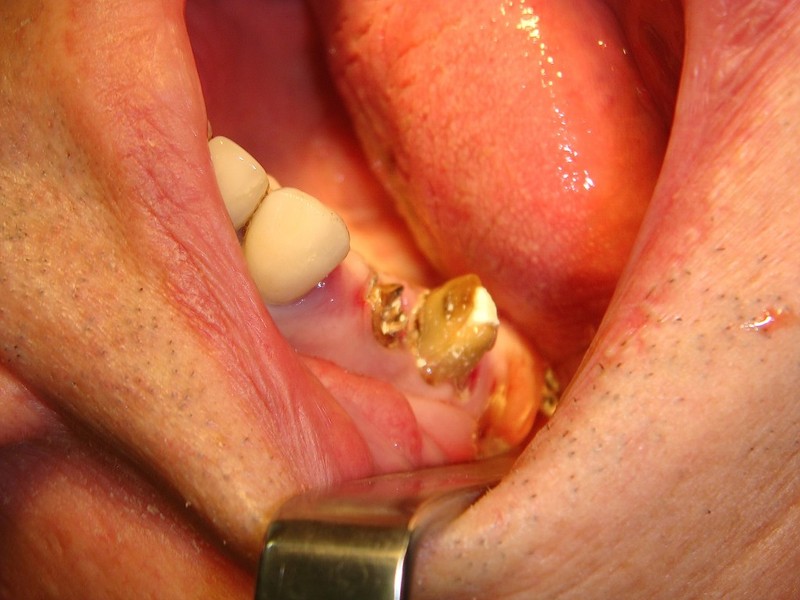

rigenerazione grave difetto parodontale a carico del 46